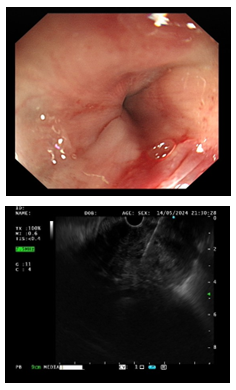

3.消化内镜中心完成首例超声内镜引导下细针穿刺活检术

5月8日, 驻疆专家史海涛成功完成新疆医院首例超声内镜引导下细针穿刺活检术(EUS-FNA),标志着新疆医院消化内镜诊疗技术迈上新台阶。

5月9日,在重症医学科副主任驻疆专家王春亚、消化内科驻疆专家史海涛、心血管内科驻疆专家韩捷、麻醉科驻疆专家袁浩峥的全力协作下,成功救治一名反复呕血伴肾衰和高血压的危重症患者,体现新疆医院多学科联合救治能力。

治疗前胃镜检查结果

治疗后胃镜检查结果